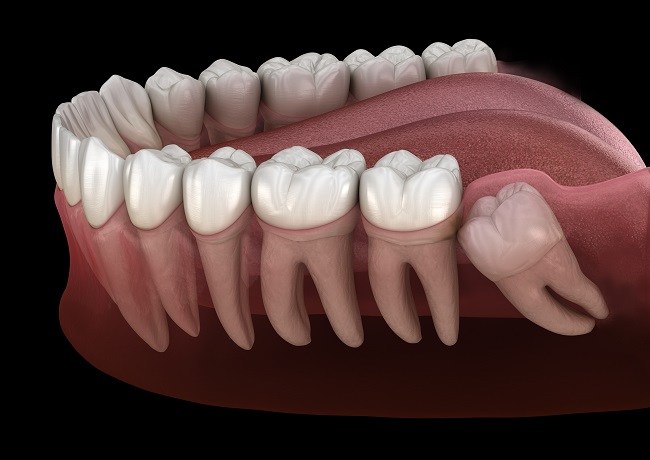

Kondisi ini dikenal dengan istilah impaksi gigi bungsu. Impaksi terjadi ketika gigi tidak bisa tumbuh sepenuhnya karena terhalang oleh gigi di sebelahnya atau oleh jaringan gusi. Akibatnya, dapat timbul peradangan dan infeksi di sekitar area tersebut. Beberapa orang bahkan mengalami demam ringan dan bau mulut akibat infeksi yang berkembang. Dalam kasus tertentu, infeksi dapat menyebar hingga ke telinga atau rahang, menyebabkan rasa nyeri yang menjalar dan mengganggu aktivitas sehari-hari.

Namun, pada kebanyakan kasus, pertumbuhan gigi bungsu tidak seimbang dengan perkembangan rahang manusia modern yang cenderung lebih kecil. Akibat keterbatasan ruang tersebut, gigi bungsu justru menjadi sumber masalah. Jika dibiarkan tumbuh miring atau menekan gigi lainnya, dapat menyebabkan gigi berjejal dan mengubah posisi gigi yang sudah rapi. Dalam jangka panjang, hal ini bisa mengganggu fungsi mengunyah, menimbulkan rasa tidak nyaman, bahkan menyebabkan gangguan sendi rahang jika tekanan terus berlanjut.

Selain itu, gigi bungsu yang tumbuh miring dapat menekan gigi di sebelahnya sehingga menyebabkan pergeseran posisi gigi, kerusakan email, atau pembentukan kantung kista di sekitar akar gigi. Jika tidak ditangani dengan benar, komplikasi tersebut bisa memerlukan tindakan bedah lebih lanjut untuk mencegah kerusakan yang lebih luas. Oleh karena itu, penting untuk selalu melakukan pemeriksaan sinar-X sebelum memutuskan apakah gigi bungsu perlu dicabut atau tidak.